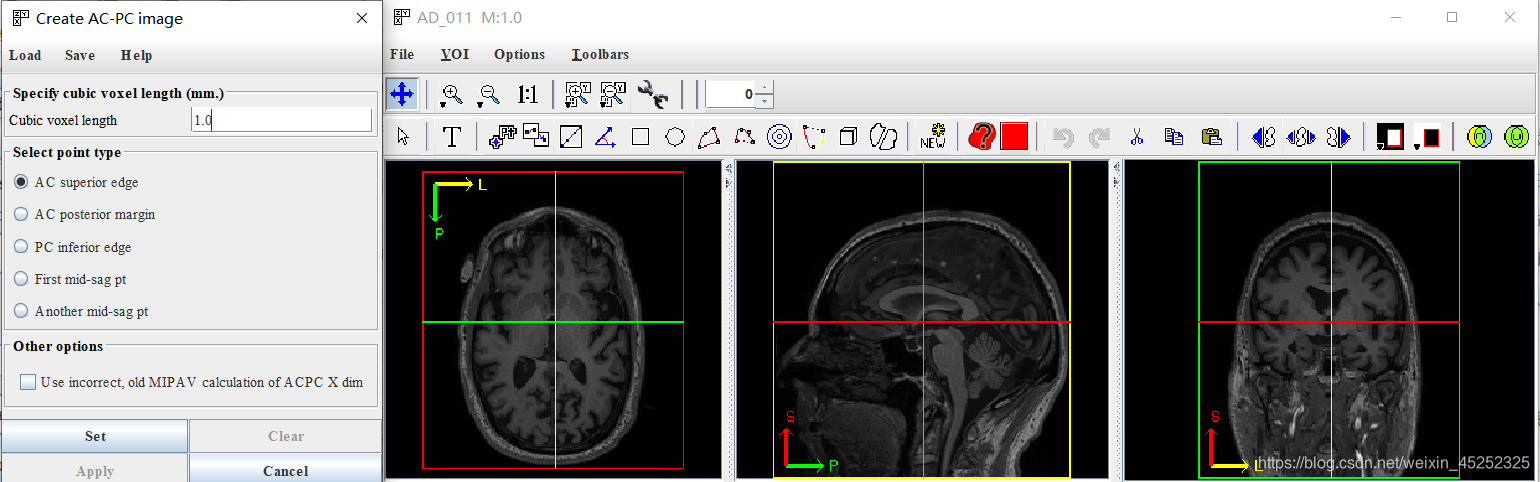

3、正式进入ACPC处理,详细教程参考,以下也是基于该pdf来做的

目标:确定5个点的位置

对于这5个点的介绍(图中显示的是矢状面):

(1) 设置精度,一般默认1.0

对于每个点,在三平面视图中的适当位置设置十字准线

(2) 第一个目标标记AC上中部和后中部

AC:

•矢状位:在穹窿下方胼胝体底部寻找AC

•冠状:寻找“胡须”

•轴向:寻找半球间的连接

① 使AC在十字准线的焦点处居中(轴向和冠状)

② 向上移动,直到AC在轴向视图中消失,然后向下移动1像素

③ 设置AC上边缘(superior edge)

④ 将焦点移回AC中间

⑤ 向后移动直到AC在冠状面上消失;然后往前1像素

⑥ 设置AC后缘(posterior margin)

尽量把图放大来选点

找到AC superior edge,点击set

找到AC posterior edge,点击set

(4)第二个目标是标记PC inferior edge

•这更难,因为PC在1毫米分辨率下显示不好

•幸运的是,PC始终位于脑导水管的顶部,这确实显示得很好(至少,如果脑脊液被MRI脉冲序列适当抑制的话)

因此,如果你看不到PC,就在脑导水管顶部找到中矢状位,标记为PC下缘(inferior edge)

(5) 第三个目标是标记两个中矢状点(胼胝体上方)(这一步在文中没有详细描述,所以有点模糊,参考另一篇参考)

First midsagittal point和Another midsagittal point,要求二者之间距离在20mm以上,一般就选择在和AC,PC同一矢状面上(在实践中,SG1和SG2的好候选者通常远离AC和PC,彼此之间也远离)